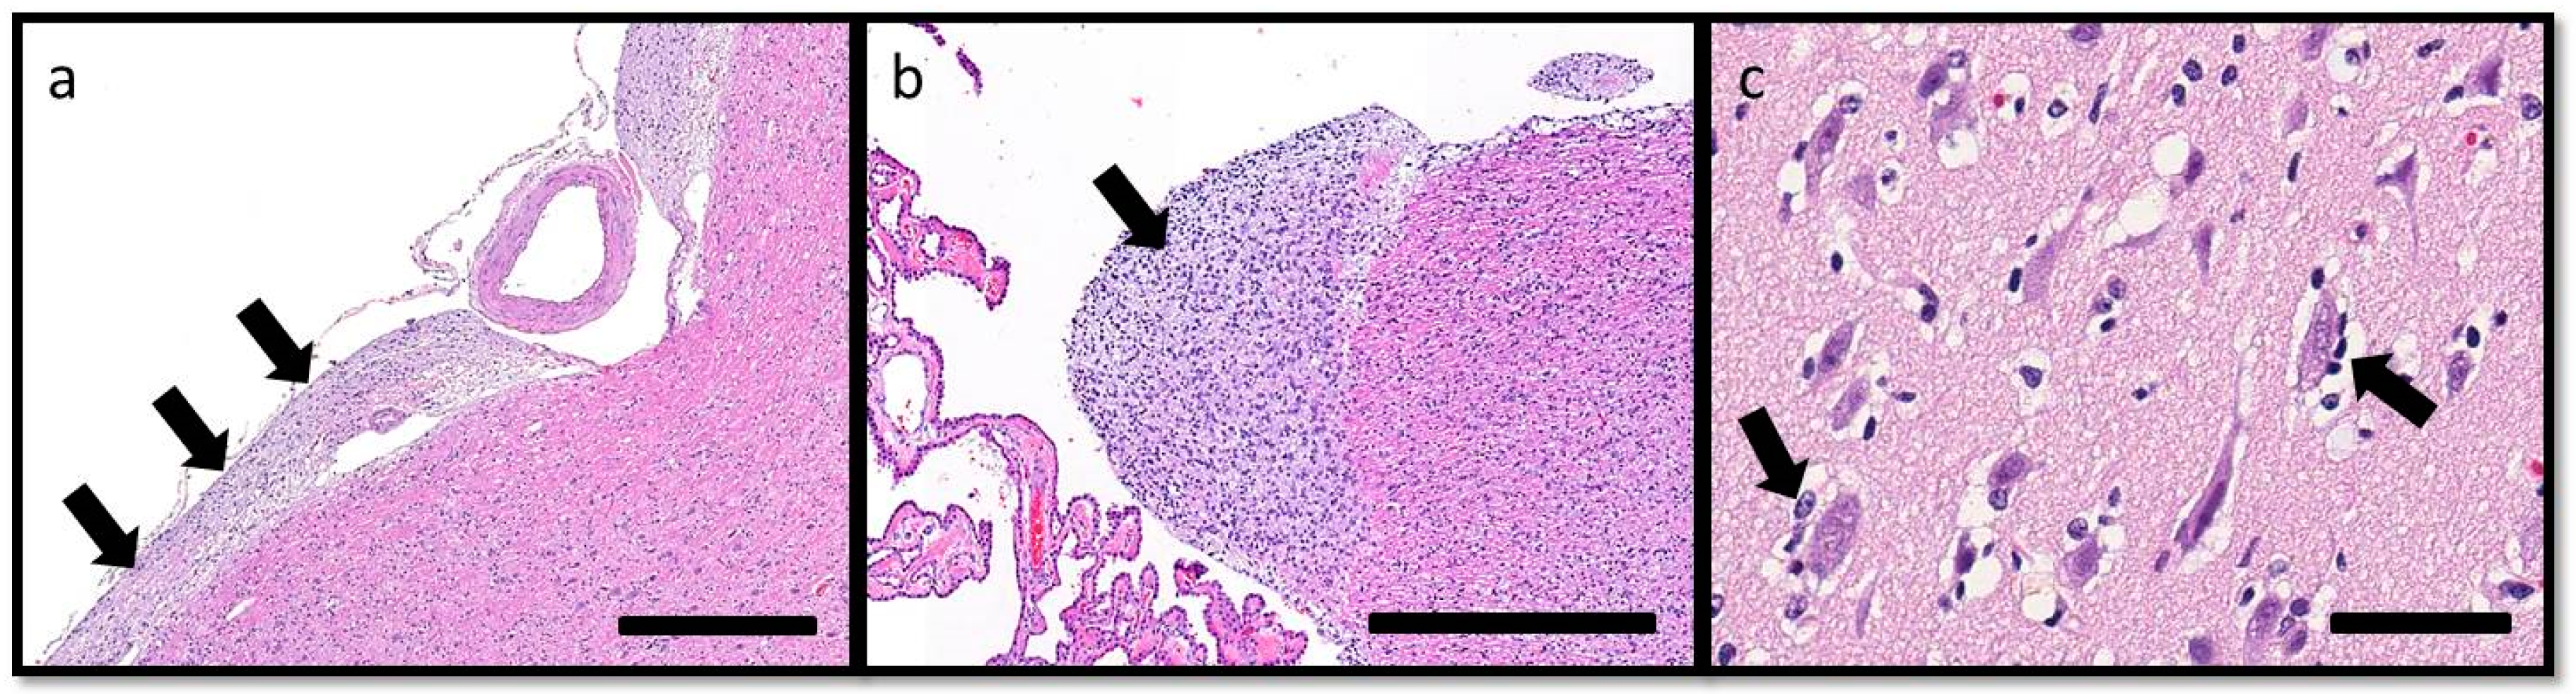

On histopathologic examination, ventral grey and white matter of the cerebrum (including the olfactory nuclei, olfactory tracts, corpus striatum, lateral septal nuclei, medial septal nuclei, thalamic nuclei and hippocampus), cerebellum, and brain stem (predominantly affecting the olivary nuclei) were bilaterally but asymmetrically infiltrated and expanded by dense sheets of neoplastic cells that merged gradually into the adjacent parenchyma, resulting in indistinct margins between normal and abnormal tissue (Figure 4a). The neoplastic cells had indistinct cytoplasm, ovoid to elongated or curved hyperchromatic nuclei, and indistinct nucleoli (Figure 4b). Anisokaryosis was mild and there was one mitotic figure per 10 400× fields. Multifocally, the neoplastic cells formed secondary structures of Scherer, including foci of subpial spread (predominantly along the ventral aspect of the brainstem; Figure 5a), subependymal aggregates (Figure 5b) with multifocal extension into and expansion of the leptomeninges, and minimal perineuronal satellitosis (Figure 5c). The neoplastic cell population was negative for Olig2, GFAP, Iba1, CD3, and Pax5. Scattered among these cells were variable numbers of GFAP-positive astrocytes, Olig2-positive oligodendrocytes, and Iba1-positive microglia. All examined sections of spinal cord were histologically unremarkable. Based on the cellular morphology, immunolabeling characteristics, and anatomical location, a diagnosis of gliomatosis cerebri was made.

Figure 5. Secondary structures of Scherer, demonstrating migration of glioma cells through the brain, include: (a) subpial spread of neoplastic cells (arrows) along the ventral aspect of the brainstem, HE. Bar = 500 μm; (b) subependymal aggregation (arrow), HE. Bar = 500 μm; and (c) minimal perineuronal satellitosis (arrows). HE. Bar = 50 μm.